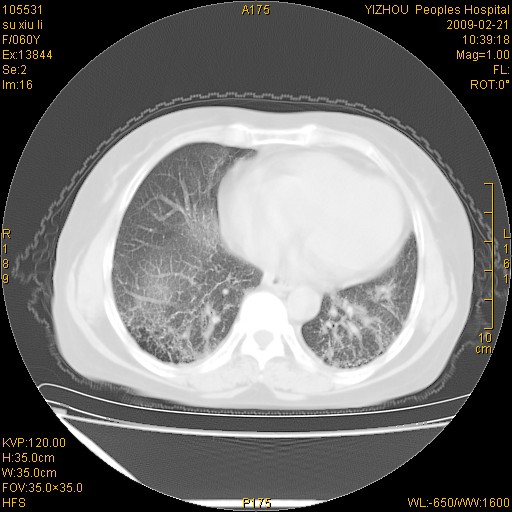

标题: CT18259:两肺间质纤维化? [打印本页]

标题: CT18259:两肺间质纤维化?

女,60岁,反复咳嗽1月。

两肺支扩,以肺为著合并双肺较广范纤维化病变。建议除外结核等病变。

间质性肺炎

两下肺支扩

符合间质感染,部分纤维化表现

特发性间质纤维化

特发性间质纤维化伴支扩!

间质性肺炎或特发性间质性肺炎